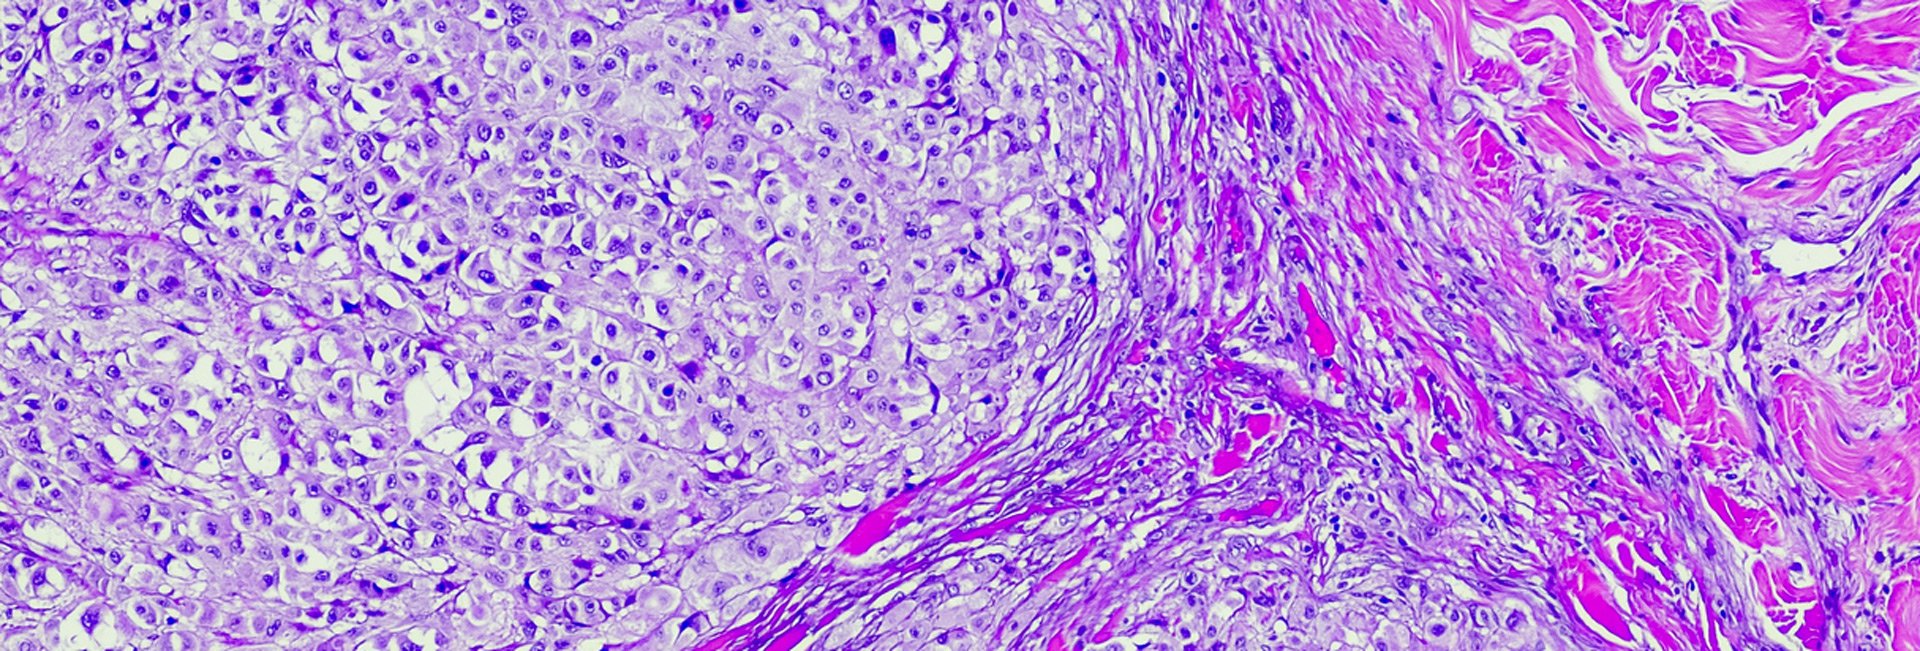

metastatic melanoma cells seen through a microscope slide

TAMPA, Fla. — Cutaneous melanoma is considered the deadliest form of skin cancer because it’s aggressive and tends to spread quickly through the body. While scientists have made significant progress in understanding the molecular mechanisms leading to melanoma development, it is still unclear how the PTEN protein regulates melanoma progression. In a new study published in Cancer Research, a journal of the American Association for Cancer Research, Moffitt Cancer Center researchers reveal how the antitumor activity of PTEN suppresses the cancer-promoting activity of the FRA1 transcription factor through the AKT signaling pathway.